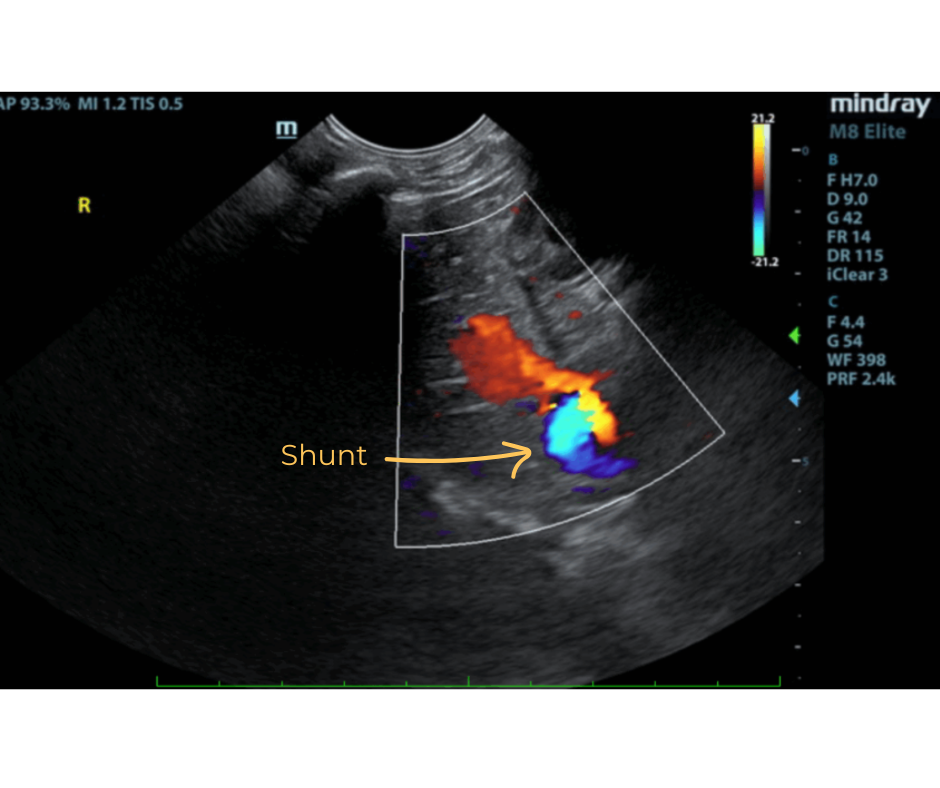

The liver was subnormal in size. The mid dorsal liver in this patient revealed an abnormal intrahepatic branch of the portal vein. This is most consistent with central divisional shunt. However, this should be further evaluated with CT. The gallbladder and common bile duct were unremarkable.

- Intrahepatic shunt – suspect central divisional or right divisional shunt

- Suspected Intrahepatic Shunt

Ultrasound can identify a small liver, abnormal vessels, altered portal vein/vena cava ratio, altered portal vein/aorta ratio, renomegaly, and urolithiasis. Identification of an IHPSS with an experienced operator has a sensitivity of 95-100%. IHPSS tend to have a large diameter and they are outlined by the liver parenchyma making them easier to identify. CT scan is used for cases that are unable to be identified using ultrasound and to correctly identify the origin and end point of the shunt for surgical planning.